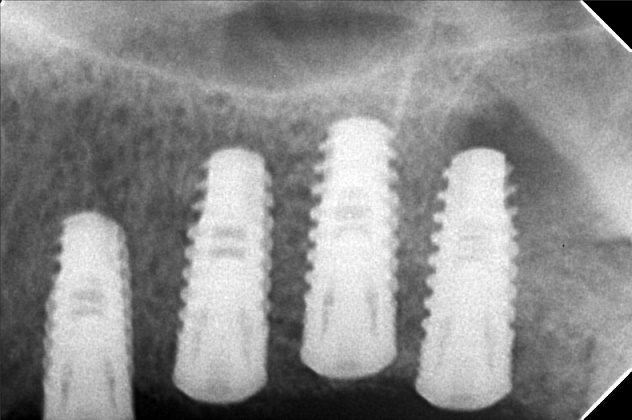

Edit Record Check our patient data records. Add patient information Patient Info Profile picture Last Name First Name Middle Name Birthdate Age Street Barangay City Country Zip Code Contact number Email Procedure 07/26/21- implant placement- 16-8.5mm 15-8.5mm/ 47/46/36/37 with prf/ cgf/ bone fillers 11/13/21 - 15 healing abutment installed- 3mm (6mm) 46/45 healing abutment installed- 6mm req for 3mm 12/17/21 - installation of abutments/ impression 12/22/21- PMMA 46/47/36/37 (12/29) final impression 2/3/22 - 4 implants 4.3x10mm lateral sinus lift LEFT 05/07/22- OP with ozone PA xray 05/13/22 recementation 22 veneers 05/31/22- Redo 23 Veneers PFZ- Temporary ***for healing abutment implants 08/12/22- installation of healing abutments 9/6/22- scan body/ intra oral scanned ***request for alginate impression *** shade A3 cervical A2 body 10/07/22- installed 4 units 24/25- with pink porcelain crown 26/27 ameloplasty mesial of 28 abutment sealed with TF Zirconia crown- screw retained 12/17/22- OP 05/13/23- xray/ozone 09/23/23- OP/AIRPOLISHER XRAY 10/13/23 -RCT #41 - flexion root opening - dressing formocresol 10-27-23- RCT #41 18.5 mm Champenol Flexion root 11-03-23- Obturation #41 MTA Fillapex, Master wire = fine 11/10/23 # 43 - veneer; emax # 42 - veneer; emax # 41 - crown; PF Z # 31 - veneer; emax # 32 - veneer; emax shade A3/ B2 11/17/23- Installation of Veneers- 43,42,31,32 (emax) Crown Zirconia- 41 Cement: choice 2 Prosapac Vacummed sheet retainer 05/25/24 OP w/ air polisher 03/29/25 OP w/ air polisher LC #42 (I) cementation repair veneer 06/13/25 Upper #23-PFZ Lower # 32,33- Zirconia bal.70k 06/18/25 installed PFZ crown #23 zirconia crown #33,#32 bal,. paid 08/08/25 Dx:peri implantitis #44/15 moldable bone-HUBT .m30 w/PRF #44 implant moldable bone HUBT .m30 w/ PRF #15 scaling and planning disinfect w/ citric acid irrigate w/ citric acid Rx: Celecoxib 400mg Tranexamic 500mg Co amoxiclav 625mg, Orahex Prednisone 10mg for 10 days 02/24/26 LC on iplant #25-Occ #23- Recement veneer 02/25/26 Repair 04/01/26 #13 DCV File 01cb0af9-a7ec-487f-a76f-2b7aa0463be3.jpeg File 2 9941df4f-eadd-49c9-a9ad-b0f3e6f2052a.jpeg File 3 2d4f20db-c762-4f0e-9fe3-4a3ecc7b62c0.jpeg File 4 a55f6852-691c-4c51-ad5c-f6f58a1f269c.jpeg File 5 a965f478-086f-4edc-bdde-4c4f9bcd41ff.jpeg File 6 d31d3680-98bc-43a6-bcb1-c3d0d4b8c1c5.jpeg File 7 roleenxray.jpg File 8 roleen_del_prado.jpg File 9 rollen_del_prado_02.jpg File 10 rpleen_del_prado_04.jpg File 11 1000005163.jpg File 12 File 13 File 14 File 15 File 16 File 17 File 18 File 19 File 20 Retain Record Retain Record Yes No Save Your Changes